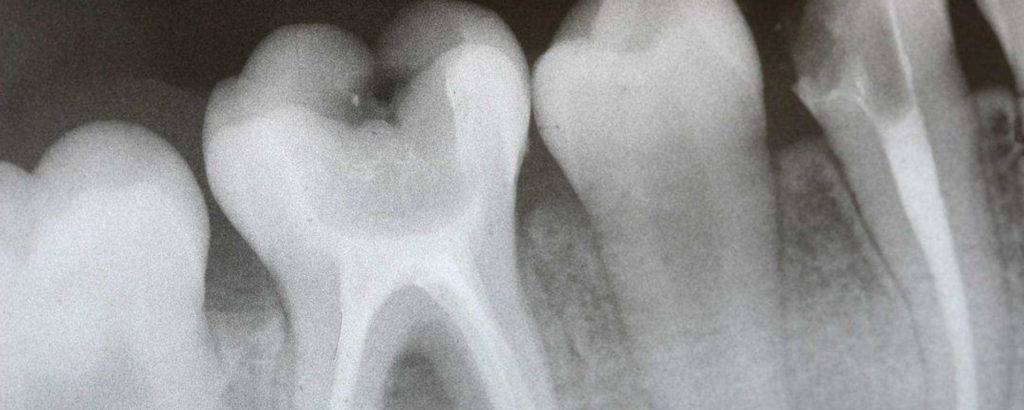

Стоматологическое исследование при кормлении грудью

Чаще всего рентген зубов при грудном вскармливании назначают для:

- выявления источника боли или причины искривления,

- просмотра местонахождения пломбы,

- обнаружения очага воспаления или кисты, а также при заболеваниях мягких тканей,

- уточнения возможности сохранения зуба,

- диагностики кариеса.

Стоматологи заверяют, что проведение процедуры при кормлении малыша грудью безопасно и никак не влияет на грудное молоко. Но если есть возможность провести исследование в хорошей клинике с современным оборудованием и минимальной дозой облучения, лучше ее воспользоваться и не подвергать риску себя и грудничка.